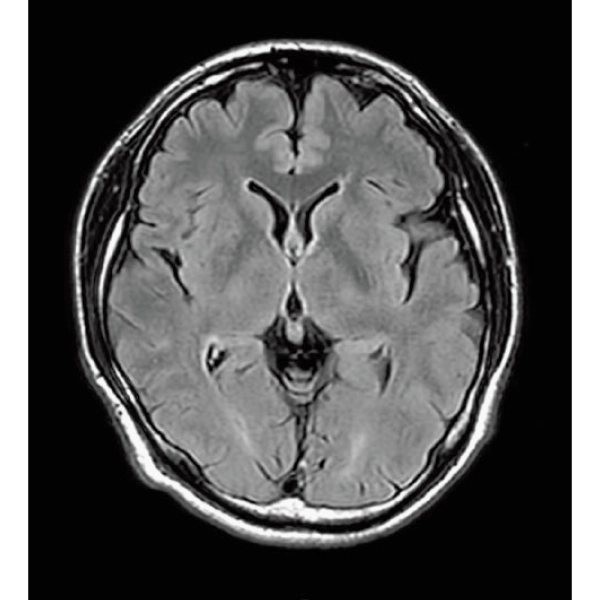

StillShot:The camera detects motion and suppresses the effects of body movement

FLAIR

T1WI Dual Echo (Out) Breath hold

RADAR:Body movement suppression technology for those who cannot hold still

T2*WI RADAR, 2:34

T2WI FatSat Respiratory gating RADAR, 2:16

3DTOF MRA RADAR (MIP)